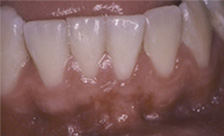

Case #3

| BEFORE | AFTER |